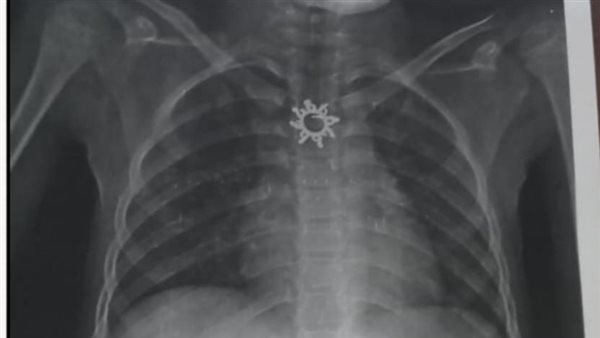

أستخرج سلسلة معدنية مدببة الأطراف ابتلعتها طفلة عمرها 9 سنوات بأبو كبير

وأوضح الدكتور أحمد البيلي وكيل وزارة الصحة أن قسم المناظير بمستشفى أبو كبير شهد نجاح مميز في إنقاذ الطفلة التي تبلغ من العمر ٥ سنوات، وقامت بابتلاع سلسلة معدنية حادة ومدببة وأطرافها قادرة على إحداث جروح أو ثقوب بالزور أو داخل المعدة، وبعد استقبالها مساء أمس الثلاثاء بمستشفى مشتول السوق المركزي، وتم التنسيق السريع من خلال مركز الخدمات الطارئة ١٣٧ بالمديرية، وتحويل الحالة بسيارة الإسعاف إلى مستشفى أبو كبير في وقت قياسي، وتم التدخل العاجل بالمنظار بعد إجراء كافة الفحوصات الطبية اللازمة لها، واستخراج السلسلة من المعدة دون أي مضاعفات، وسط متابعة وتدخل فوري من الفريق الطبي بقيادة الدكتور محمد عصام خلال الفترة المسائية.